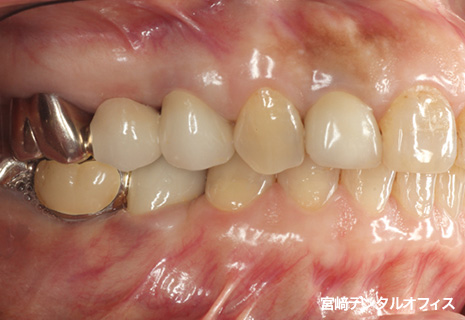

全顎的治療

術前

術後

インプラント治療